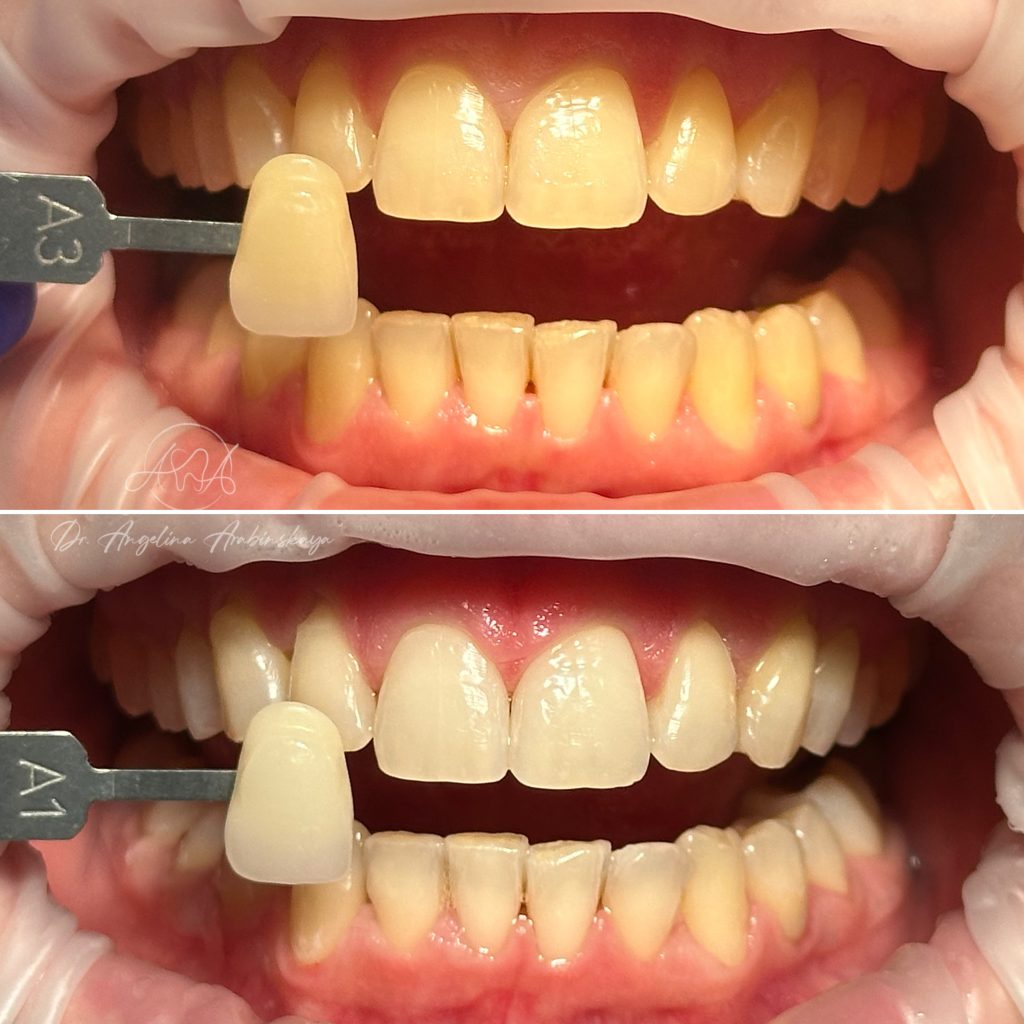

• Профессиональная отбелка зубов системой ZOOM,BEYOND

2024 год – «Отбеливание от «А» до «Я» Александр Кирманов